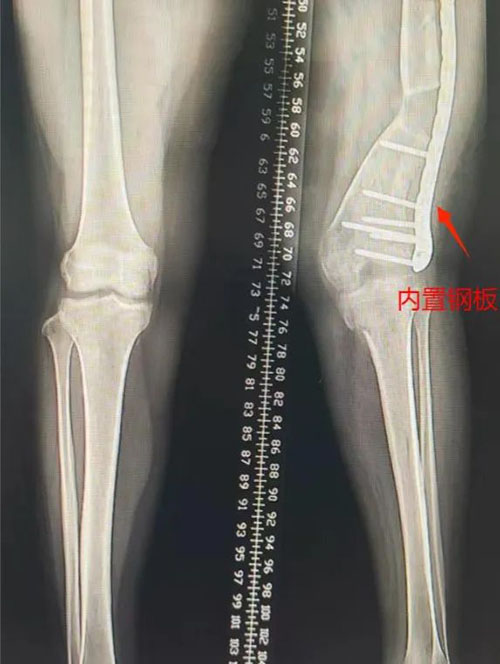

第二步:经过第一步的治疗,左下肢外翻畸形基本纠正,力线恢复,尽早拆除Illizarov架,予行切开钢板内固定术。

▲术前畸形,拆除外固定架,钢板内固定